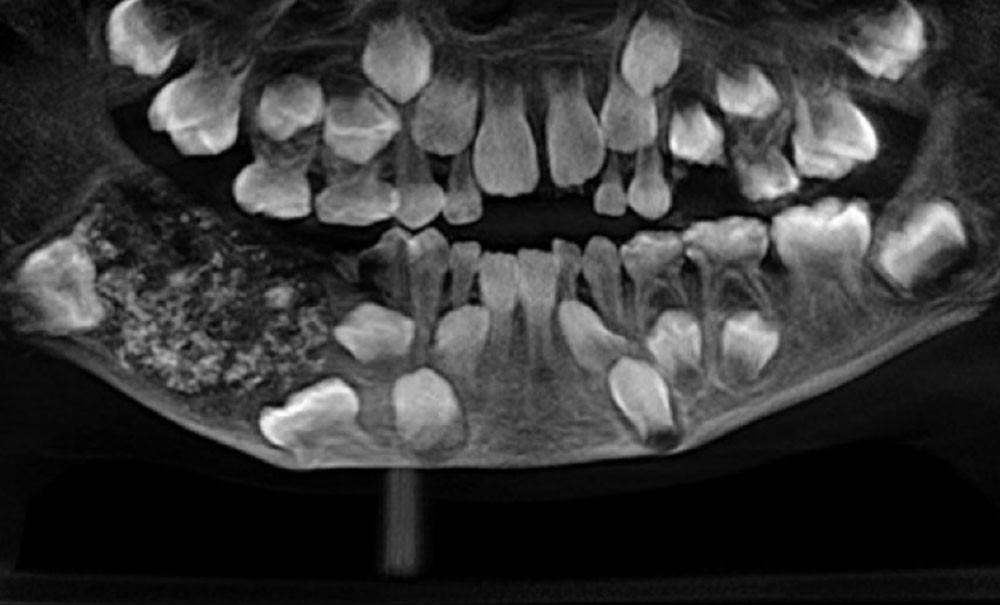

Les praticiens du département de chirurgie buccale et maxillo-faciale du Saveetha Dental College and Hospital situé dans la ville de Chennai, dans le sud-ouest de l’Inde, ont retiré un nombre record de 526 dents et bourgeons dentaires dans la bouche d’un garçon de sept ans, rapporte un communiqué de l’hôpital début août.

L’excroissance de 200 g se situait au niveau de l’os de la mandibule droite. Il a fallu 5 heures pour retirer toutes ces petites dents dont la taille variait de 1 à 15 mm mais qui, toutes, comprenaient « une couronne recouverte d’émail et une structure ressemblant à une racine », précise l’hôpital.